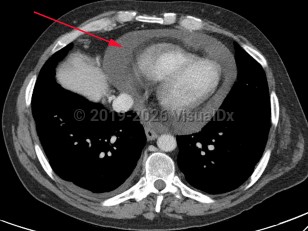

Pericardial effusionPericardial effusion